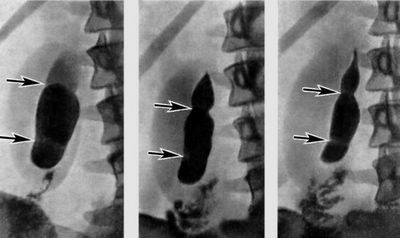

На УЗИ определяется структура органов брюшной полости, их форма, размеры, контуры, однородность паренхимы, наличие полостей и других образований. Основной признак диффузных изменений поджелудочной железы – это повышение или снижение ее эхогенности. Это значит, что паренхима органа сильнее или слабее, по сравнению с нормой, отражает ультразвуковые волны.

При остром панкреатите на УЗИ наблюдают увеличение размеров органа, а также снижение его эхогенности. При хроническом панкреатите снижение плотности определяется без изменения контуров органа. Если же эхогенность повышена, такие диффузные изменения поджелудочной железы чаще всего свидетельствуют о перенесенном ранее воспалительном процессе.

Заболевшему человеку нужно сделать УЗИ, при котором видны все спайки и изменения желчного пузыря. Желчь становится густой, появляется в пузыре песок, что ведет к серьезному нарушению пищеварения.